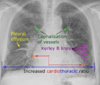

¿Cómo se calcula el índice cardiotorácico?

A + B / C

128

Índice cardiotorácico normal

< 0.5

Rx en insuficiencia cardiaca

A: edema alveolar B: líneas B de Kerley C: cardiomegalia D: dilatación de vasos en lóbulos superiores E: derrame pleural

130

Insuficiencia cardiaca